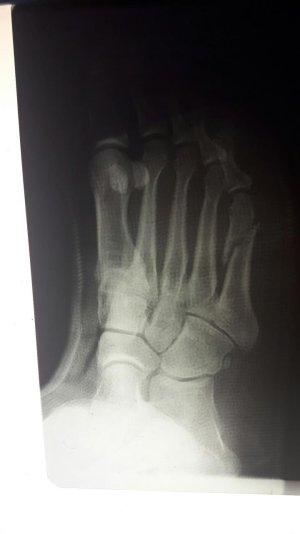

Отрывной или Джонса? Если отрывной, то так бывает

Здравствуйте. Мне 38 лет. Перелом 5-ой плюсневой.

Приложенные снимки - на следующий день после случившегося. Сразу в гипс на 5 недель. Ни в травмпункте, ни в поликлинике лечащий врач даже на упоминали операцию.

Только в травмпункте доктор сказал "... с незначительным смещением, поэтому просто гипс на месяц."

Посмотреть вложение 13116 Посмотреть вложение 13117